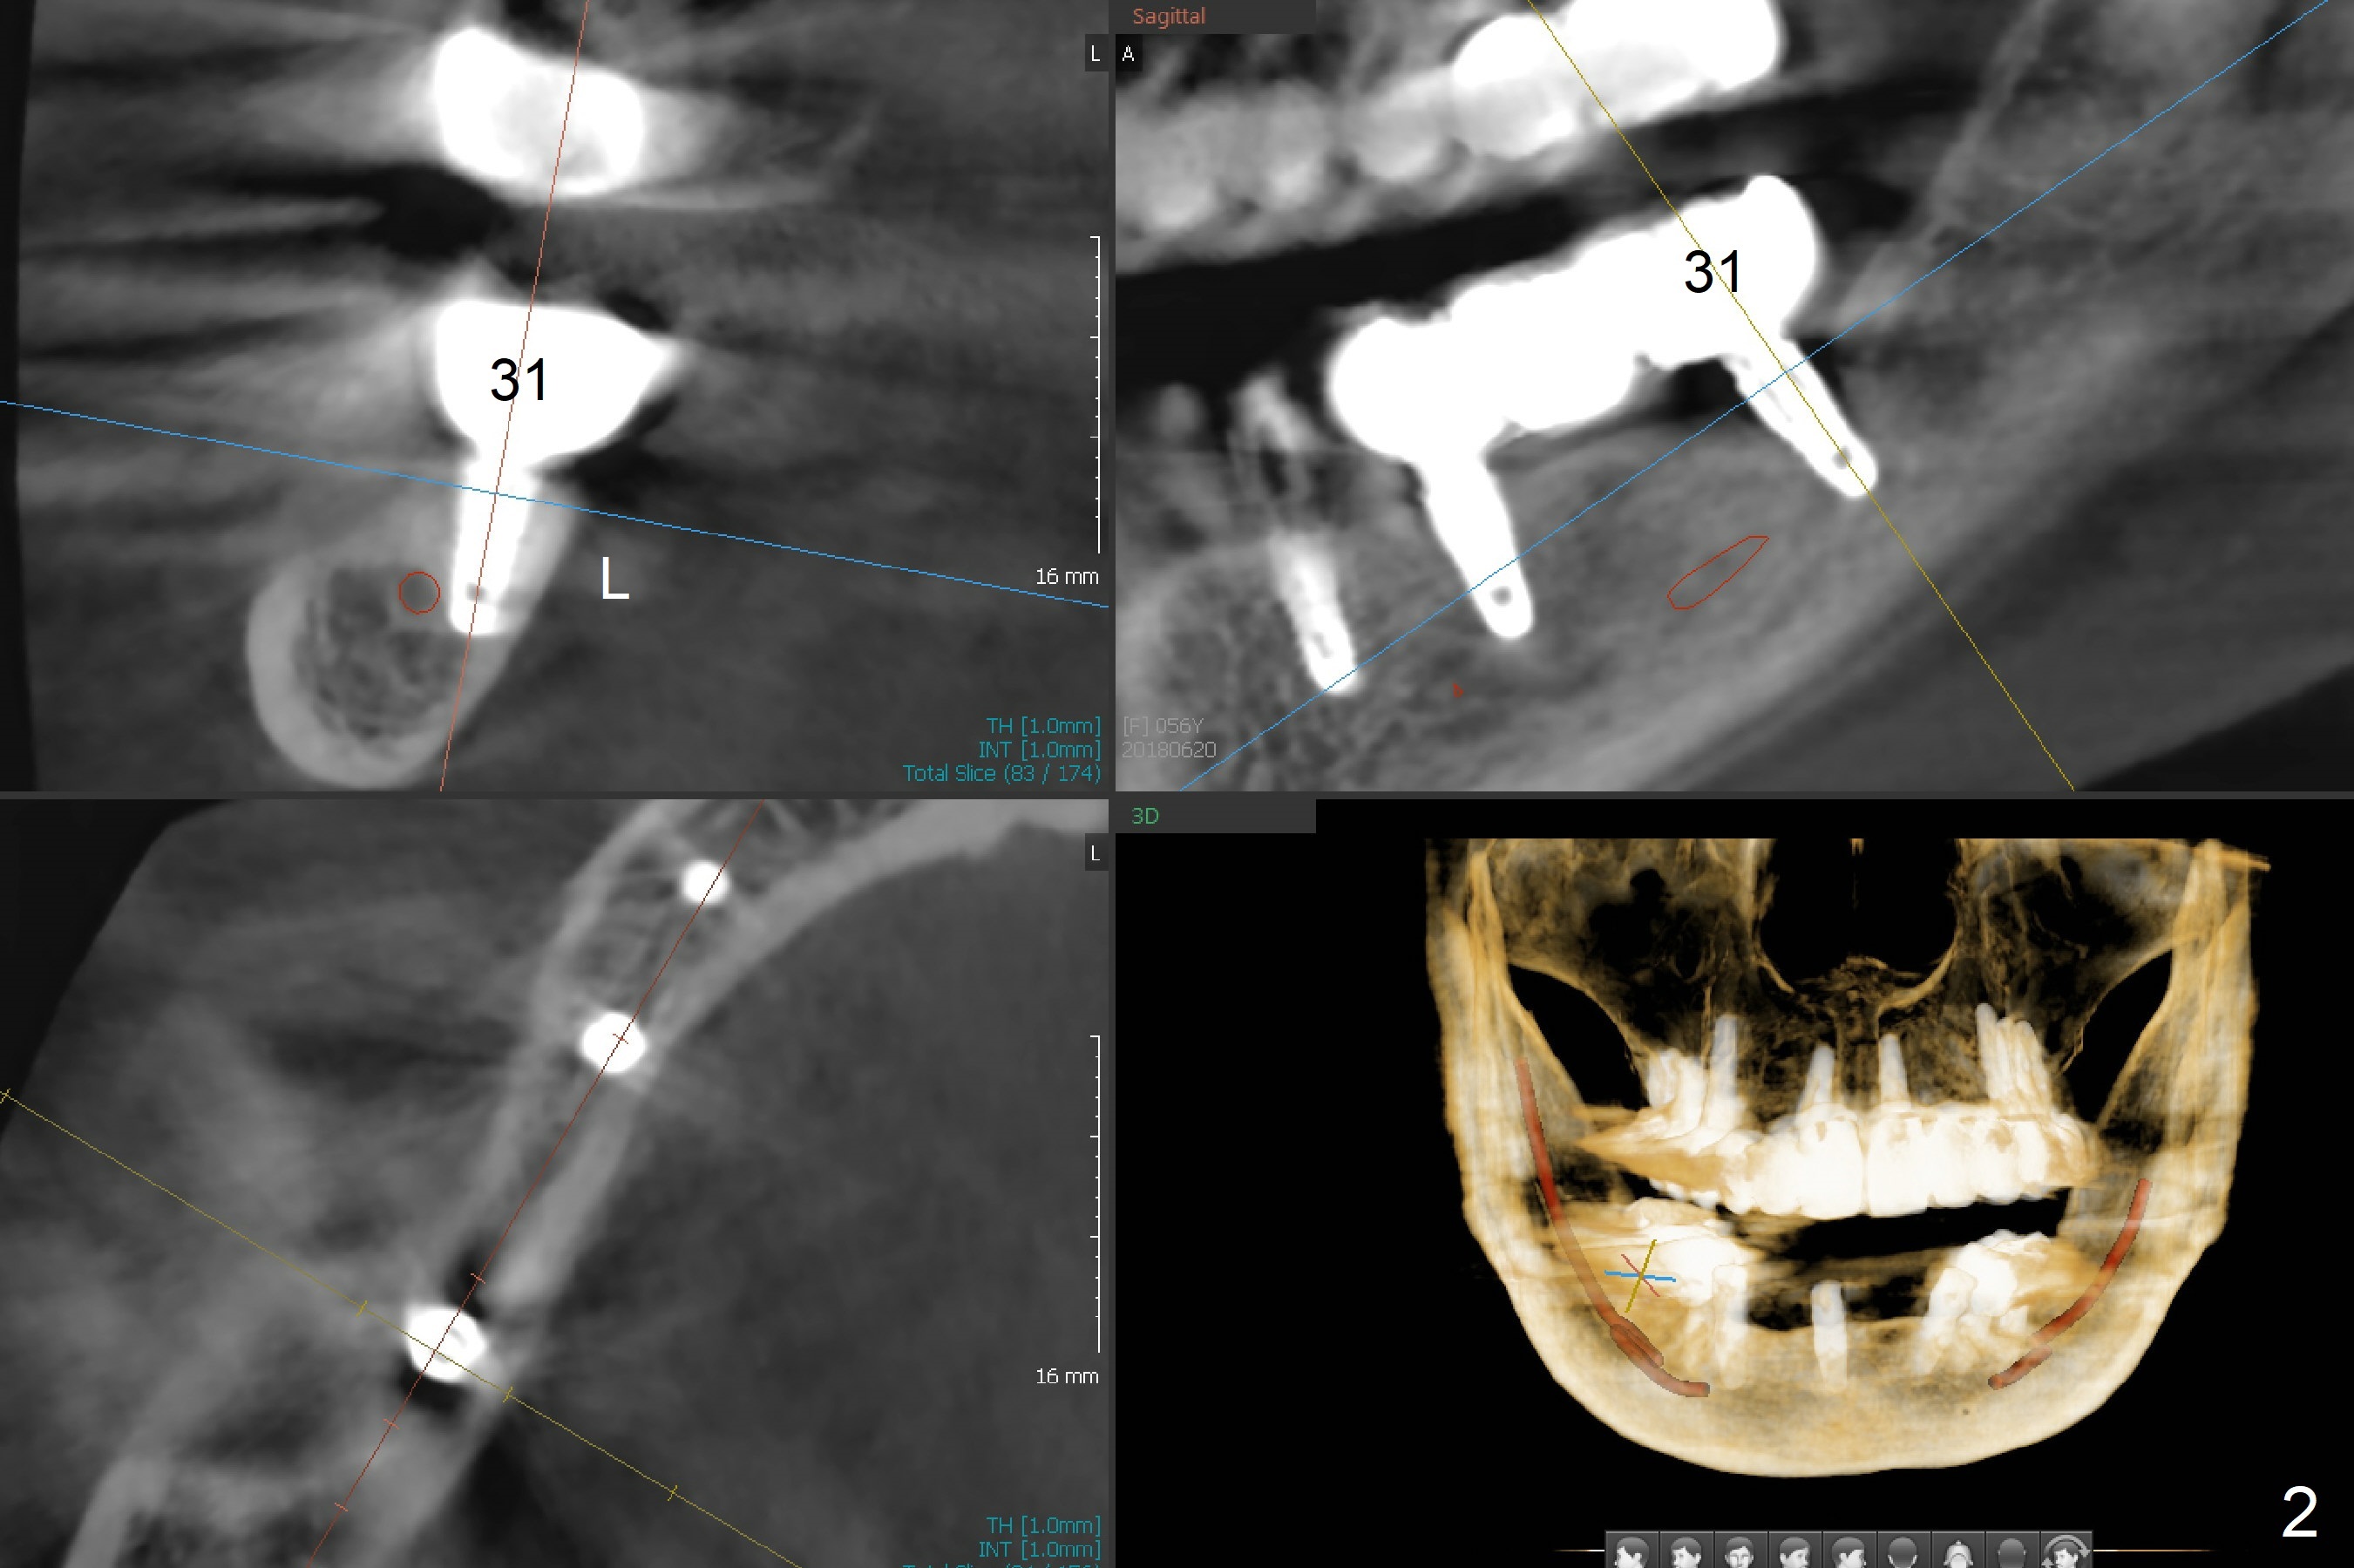

A 56-year-old woman with atrophic jaws requests redoing lower implant restoration (in function 1 year) for cosmetic reason and placing an implant at #19 (because she could not masticate on the left, Fig.1). While the 3.8x8.5 mm implants at #31 and 20 are placed lingual (L) to the Inferior Alveolar Canal (IAC, Fig.2,3) "free hand", can a 4x7.3 mm implant (Fig.4 blue outline) be placed buccally (B) at #19 with a guide?